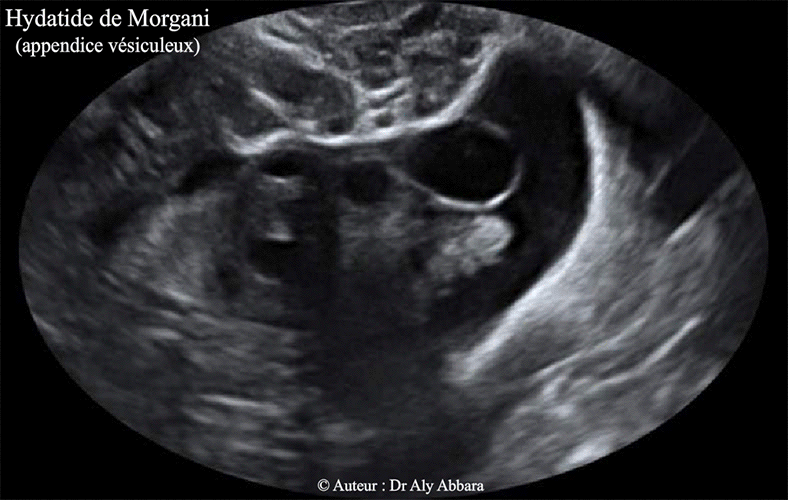

L'appendice vésiculeux

| L'appendice vésiculeux

(anciennement l'hydatide pédiculée

de Morgani) : Il s'agit d'une formation appendue à l'une des franges du pavillon tubaire ; elle prend l'aspect d'une vésicule ronde ou ovoïde mesurant de quelques mm à 20 mm, à paroi fine translucide. Cet appendice se développe aux dépens des vestiges embryonnaires de la portion supérieure du système de Wolff, et précisément, du 1e ou du 2e canalicule mésonéphrotique du corps de Wolff (ou le mésonéphros = rein primitif transitoire). Dans le cas présenté dans cet article, l'appendice vésiculeux vestigial n'est pas appendu à une frange du pavillon tubaire : en effet son pédicule est attaché à la trompe gauche au niveau de sa portion médiane. |